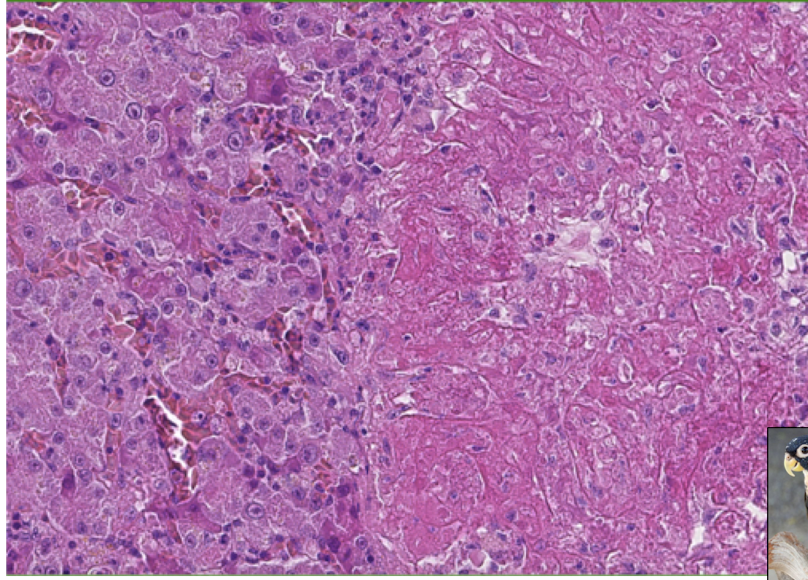

What is the morphologic diagnosis of this histological slide? What is a likely etiologic diagnosis?

Acute severe heterophilic necrotizing multifocal hepatitis

Etiological diagnosis: Bacterial hepatitis

What is being indicated by the yellow arrows? The blue arrow?

Yellow arrow: macrophages with unicellular debris.

Blue arrow: Dead heterophils